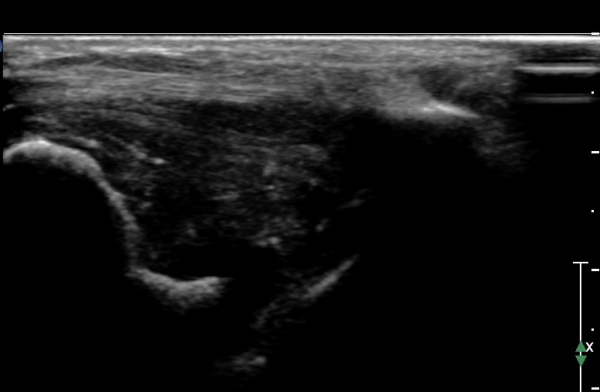

ÃÊÀ½ÆÄ °Ë»ç :  ¹ß¸ñ ¾ÕÂÊ Á¾´Ü¸é°Ë»ç¿¡¼­ ƯÀÌ ¼Ò°ß º¸ÀÌÁö ¾Ê´Â´Ù(»çÁø 1)